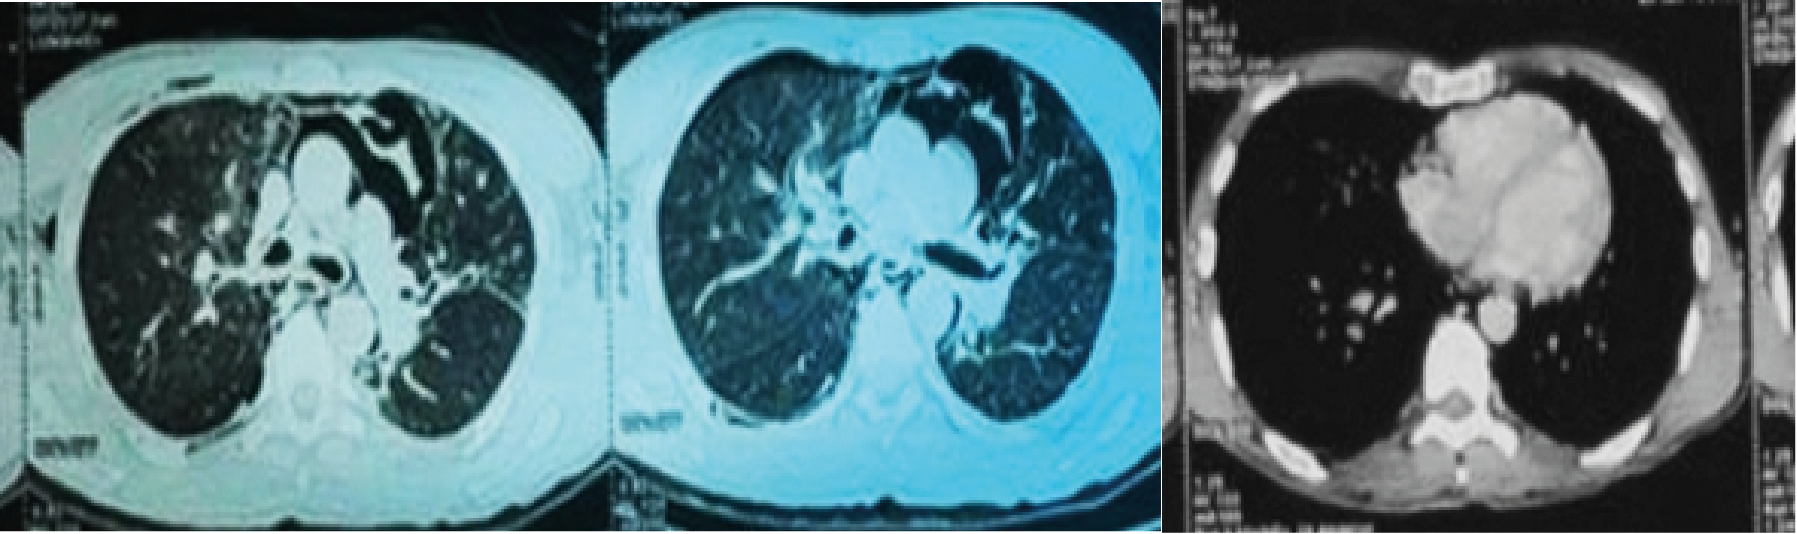

Initial management included insertion of two peripheral venous lines, fluid resuscitation, oxygen therapy, and decompression of the right pneumothorax. The thoracic injury assessment revealed multiple pulmonary contusions, a moderate right pneumothorax, a small left pneumothorax, a right posterior basal hemothorax, and a large pneumomediastinum on chest CT scan (Figures 1, 2, and 3). In addition, extensive subcutaneous emphysema was noted in the thoracic and dorsal softs tissues.

Figure 1-3: Chest CT scan.